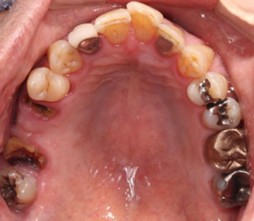

20代 男性

治療前

- 20代/男性

- 患者の具体的な症状

- 1年前に左上12 右上1の根の治療をし、その後放置していたら、左上2が破折した。

左上2インプラント補綴 左上1右上1オールセラミック装着。

歯根破折と虫歯による痛み、審美障害を主訴として来院。 - 検査方法

- コーンビームCT、レントゲン撮影

- 診断結果

- 左上2 歯根破折

- 治療詳細

- 左上抜歯後、インプラント埋入1本

骨造成あり 局所麻酔

インプラント治療後、左上1右上1セラミック修復2本 - 通院回数

- 9回

- 治療期間

- 12か月